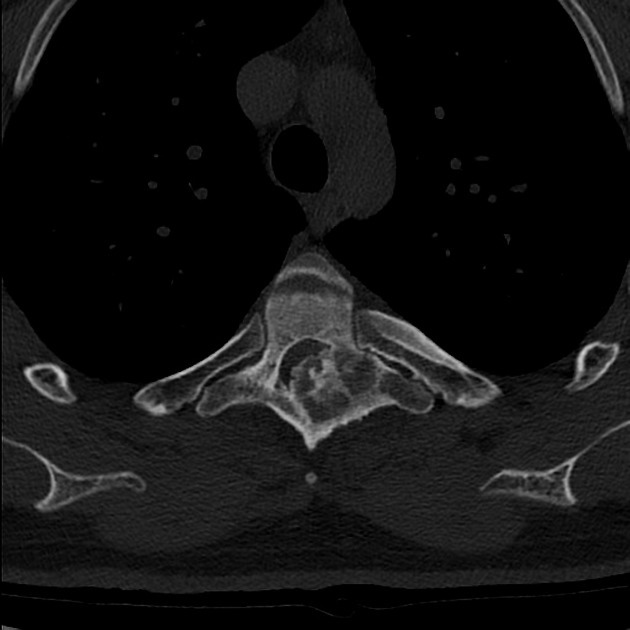

Imaging features of Osteoblastoma

1. bone-forming tumours that may be locally aggressive. Compared to their histological relative, the osteoid osteoma, they are larger (>2 cm) and more frequently affect the axial skeleton.

- well-defined tumour, predominantly lytic, with a rim of reactive sclerosis. tend to be expansive. possibly soapbubbly appearance with internal mineralization/matrix

- >2 cm in size on imaging

- may see buttressing periosteal rxn in long bones

- an associated soft tissue mass may also be present (ddx osteosarcoma)